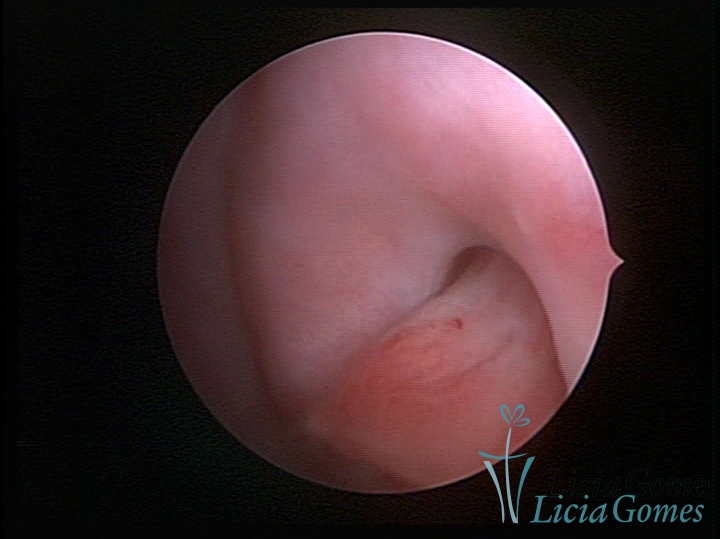

PÓLIPOS ENDOCERVICAIS

São tumores benignos, resultantes da proliferação focal reativa aos processos inflamatórios ou à situações de hiperestrogenismo, e podem ter sésseis (com a base de implantação larga) ou pediculados do epitélio.